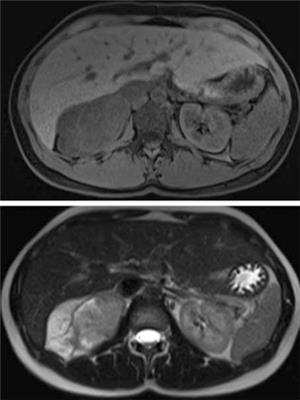

Se completó el estudio imagenológico con una resonancia magnética que no aportó nuevos datos de valor diagnóstico (figura 2).

Figura 2: Resonancia magnética. Fases T1 y T2.

Si bien se describen algunas características tomográficas (lesión sólida, bien definida, pudiendo ser lobulada, hipodensa, encapsulada y hasta en un 40% a 60% tener calcificaciones), al igual que en la resonancia magnética (hipointensos en T1 y heterogéneos e hiperintensos en T2) en general no son patognomócos1.